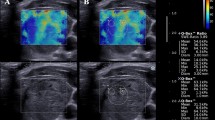

Whereas, the nodules that resulted malignant at histology had VTQ values with a mean of 3.751 ± 1.485 m/s, which was significantly higher than the value of benign nodules (2.141 ± 0.392 m/s; P < 0.001) and also higher than the value of the surrounding normal thyroid parenchyma (2.106 ± 0.491 m/s; P < 0.001). According to ROC curves (AUROC = 0.86 for Reader 1; 0.81 for Reader 2) sensitivity, and specificity for each reader were respectively 90 and 75 % for a cut-off value of shear wave of 2.455 m/s for Reader 1; 90 and 72 % for a cut-off value of shear wave of 2.365 m/s for Reader 2 (as shown in Figs. 1, 2; Table 1). The PPV and NPV for each reader were respectively 90.91 and 96.55 % for Reader 1; 90 and 95.90 % for Reader 2. Interobserver agreement was in the range considered good (k = 0.75). Intraobserver agreement was in the range considered good for benign nodules (k = 0.65 for more experienced reader and 0.63 for less experienced reader); and in the range considered good for malignant nodules (k = 0.65 for both readers). Figure 3 is an example of a benign nodule, and Fig. 4 of a malignant one.

Baseline US shows a well marginated, prevalently hyperechoic nodule with hypoechoic capsule (a) which at color-Doppler presented Pattern III and at ARFI 1.89 and 1.56 m/s of shear wave velocity, respectively, for operator 1 (c) and operator 2 (d). Histology after surgery demonstrated that the nodule was benign nodular hyperplasia